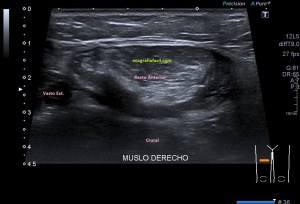

Es muy útil para lesiones que han crecido mucho y no podemos conjugar en una sola imagen, por ejemplo, un lipoma, cuando superan la medida de la huella de la sonda no son medibles, hay que usar «panoramic view», y como este caso, otros muchos.

En la imagen 3 ves una imagen de un lipoma, mide 7 cms, la huella de la sonda mide 5cms, la «panoramic view» posee una regla centimetrada que sigue el contorno de la imagen, justo en la profundidad de la misma y lo marca la flecha amarilla. La profundidad la marca la flecha roja y la flecha blanca marca el rango centimetral de los 5cms, fíjate que la línea blanca es ligeramente mayor cada 5 cms. Sirve de referencia, como en la imagen 4 donde ves una colección en el glúteo de más de 10 cms.